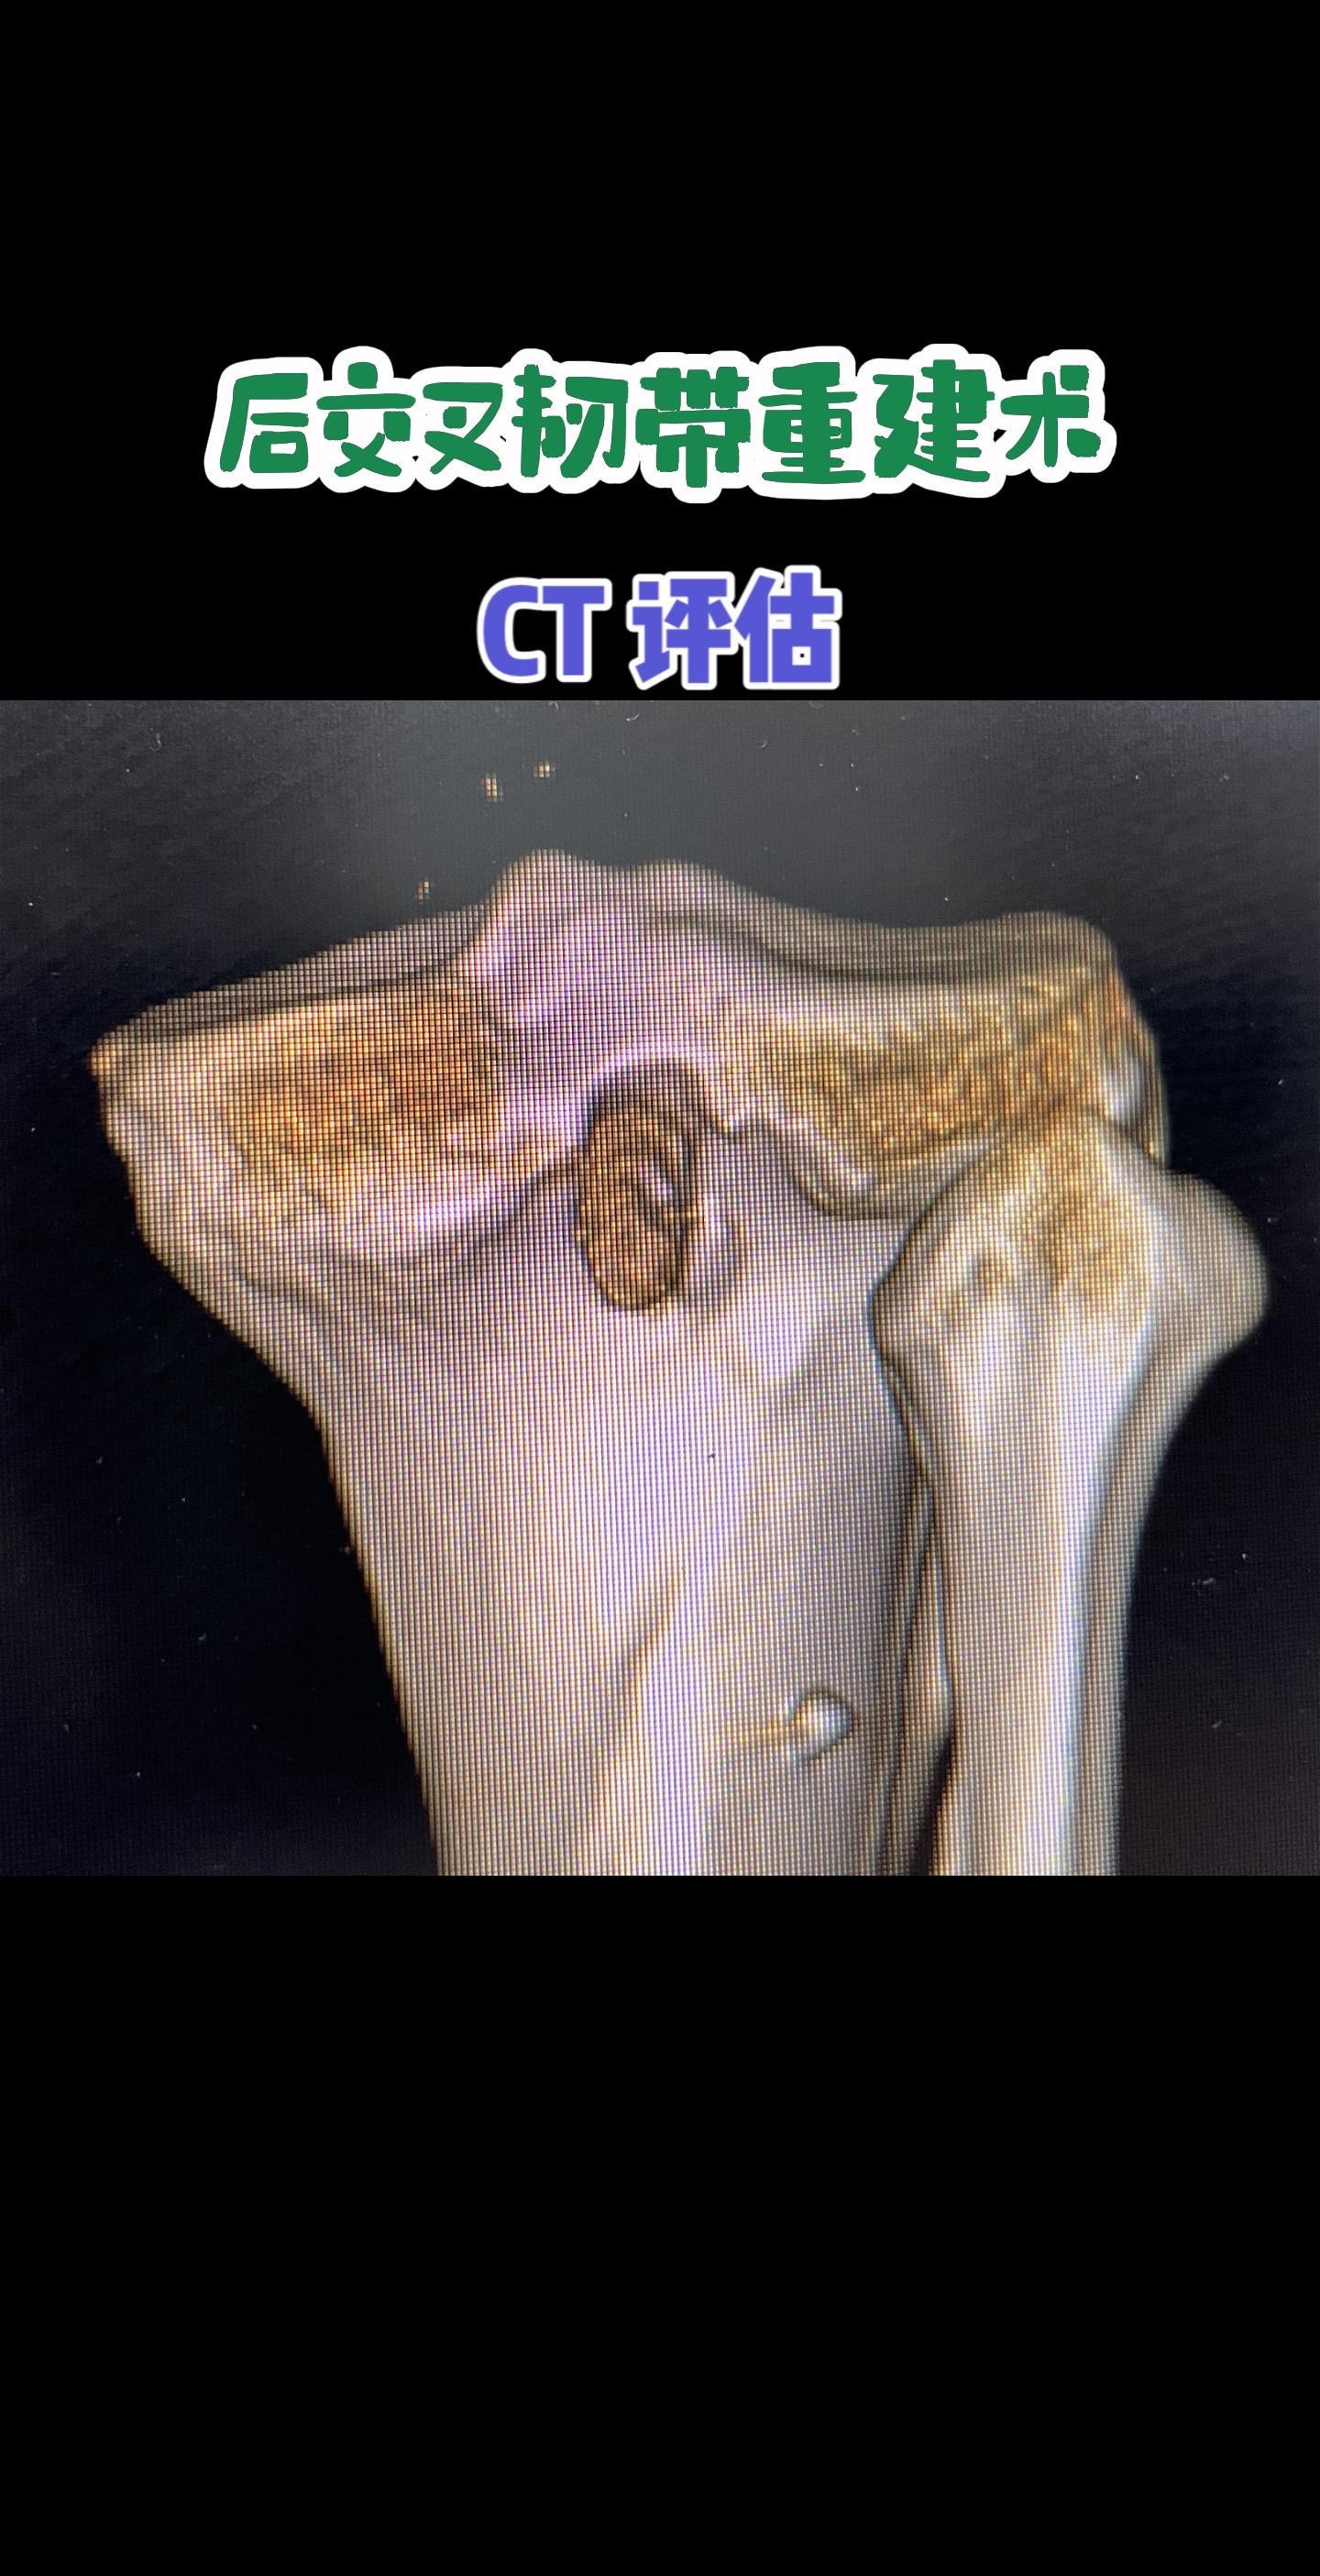

后交叉韧带重建术后影像评估。每一条韧带,都是膝盖的隐形安全带。而精准重建,就是给关节最可靠的浪漫守护。